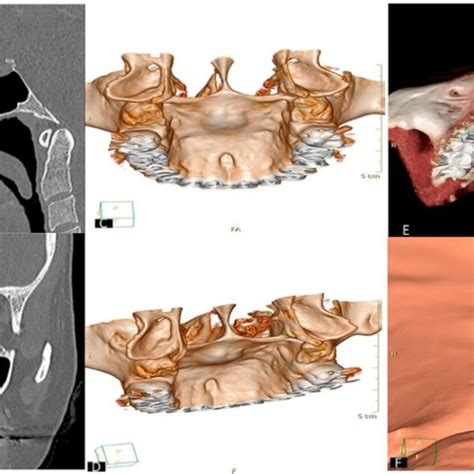

Para poder reconocer estos abscesos, el dentista puede realizar una radiografía, una tomografía computarizada (TC) o una resonancia magnética (RM).